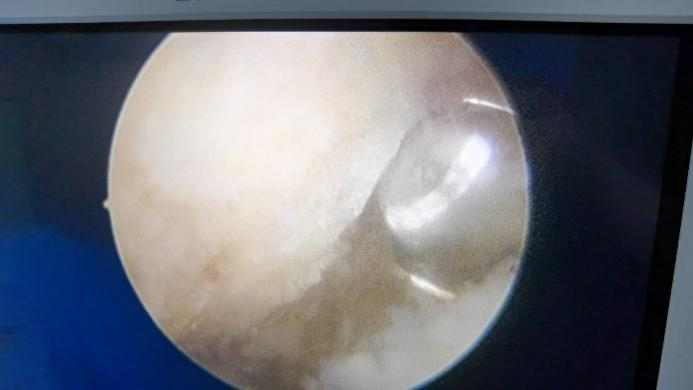

术中使用磨钻磨除骨刺

1 精准“视”界,直击病灶

关节镜如同一双“火眼金睛”。医生仅在足跟处开2个约0.5厘米的“针孔”样切口,将高清摄像头伸入关节腔内。放大的视野能清晰显示骨刺的位置、形态以及被卡压的筋膜组织,真正做到“指哪打哪”,精准磨除骨刺,松解紧张的足底筋膜。